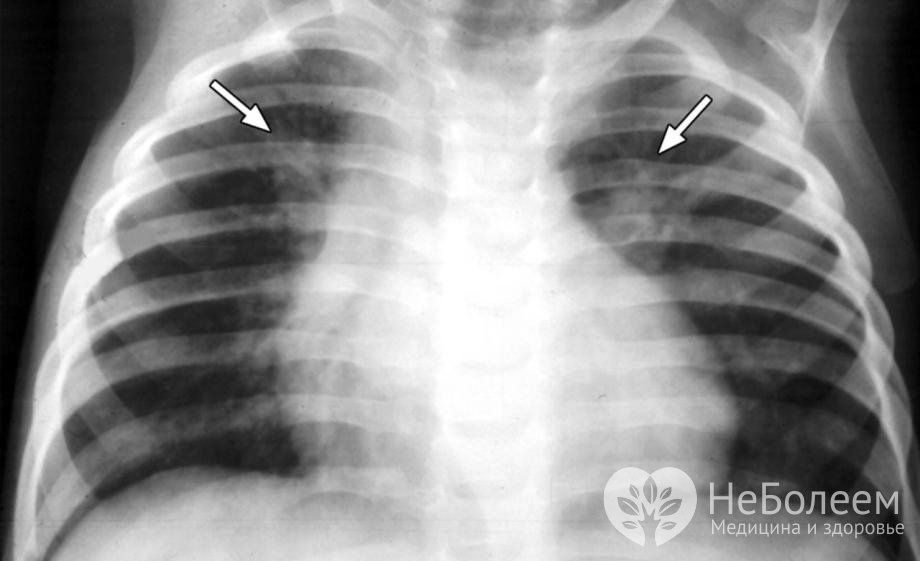

В целях уточнения диагноза проводится рентгенография легких. При поражении паренхимы на снимках просматриваются затемнения различной величины и локализации, смещение плевральных листков и расширение синусов, а в случае распространения воспалительного процесса на интерстициальную ткань – усиление легочного рисунка.

Основной метод диагностики двухсторонней пневмонии – рентгенография легкихОбщий анализ крови показывает повышение СОЭ до 30–50 мм/час и лейкоцитоз с увеличением доли палочкоядерных клеток в лейкоцитарной формуле до 6–30%. Микроскопия и бакпосев мокроты и смывов носоглотки позволяют выявить тип возбудителя и определить чувствительность данного штамма к антибактериальным и антивирусным препаратам.